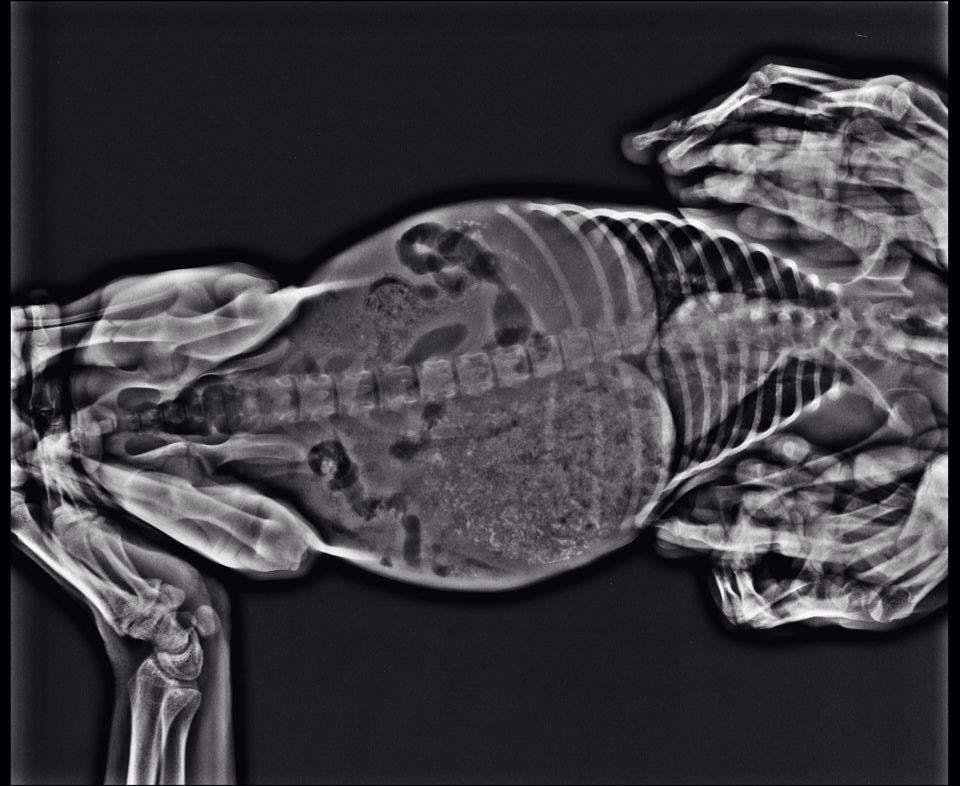

Το κουταβάκι που βλέπετε στις φωτογραφίες εντοπίστηκε χθες στο Άκτιο να κλαίει από τους πόνους κοντά στα διόδια της υποθαλάσσιας σήραγγας καθώς όπως αποδείχτηκε έχει σπασμένα τα δύο πόδια του ενώ είναι χτυπημένο και στην κοιλιά. Το πως τραυματίστηκε το ζώο παραμένει άγνωστο αν και σύμφωνα με τον κτηνίατρο Νίκο Ρώσσο, που το εξέτασε, κάποιος είναι πολύ πιθανό να το το κλώτσησε.

Η Δώρα Τσάτση μέλος του σωματείου «Παρέμβαση για τα Ζώα - Πρέβεζα» εξήγησε στο www.zoosos.gr ότι ο κ. Ρώσσος τους είπε πως είναι απίθανο το κουταβάκι, που ζυγίζει μόλις τέσσερα κιλά, να χτυπήθηκε από όχημα καθώς δεν έχει σημάδια και αυτά τα τραύματα προκαλούνται μόνο από κλωτσιά.

Εξαιτίας του νεαρού της ηλικίας του κουταβιού δεν θα γίνουν όλες οι επεμβάσεις ταυτόχρονα. Αρχικά θα χειρουργηθεί στην κοιλιά και στην συνέχεια θα ακολουθήσουν οι επεμβάσεις στο πίσω πόδι του που έχει σπάσει σε δύο σημεία και στη συνέχεια στο μπροστινό.